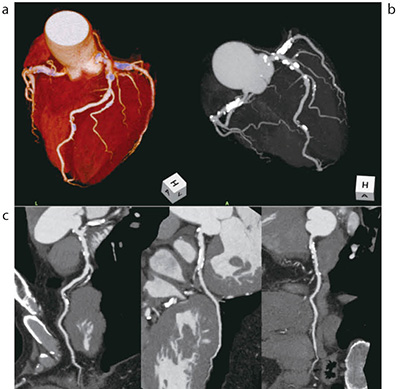

当センターでは、通常、VR、Angio Graphic View、CPRを画像提供している。CPRは、AHA分類に基づき番号を振って画像作成を行い提供している。また、どの冠動脈のCPRを作成したのかを作成者以外が見てもわかりやすくするために、Tree VRに冠動脈の番号を追記したものを合わせて画像提供している。図3の症例は、心臓超音波検査で異常が指摘され、冠動脈狭窄を除外する目的で心臓CT検査を施行した症例である。冠動脈に冠動脈石灰化スコアであるAgatston Score2000以上の高度石灰化を認めた。LADに50%程度の狭窄を認めた。

図3 冠動脈狭窄除外目的の心臓CT

a:VR b:Angio Graphic View c:CPR(LAD/LCX/RCA)

石灰化スコアが2000以上の症例であったが、CPRでも内腔の評価が可能であった。また、このような症例においても冠動脈の自動認識がきちんとされており、画像処理時のサポートとして有用である。

図4の症例は、冠動脈バイパス術後フォローで心臓CT検査を施行した症例である。冠動脈の評価はもとより、バイパスとの吻合部も明瞭に観察できている。冠動脈バイパス術後の退院前検査では、冠動脈造影と比較して、ワークステーションを用いて画像処理を行ったVRなどは、被検者にとってもわかりやすい画像であり、術後の説明用の画像としても活用されている。また、定期的なフォローアップとしても、冠動脈造影では入院して検査を行う必要があるが、心臓CT検査では外来検査として行うことが可能であり、多くの症例で定期的なフォローアップ目的には心臓CT検査を行っている。

図4 冠動脈バイパス術後フォロー

a:VR b:CPR(LITA-LAD)

冠動脈バイパス術後(LITA-LAD/SVG-HL-OM)の症例。

提示したCPR画像における赤い丸は吻合部を拡大表示している。